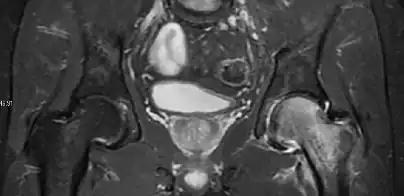

Figure 8:

X-ray of a patient with transient osteoporosis of the left hip showing osteoporosis.[1] -

Coronal stir imaging in transient osteoporosis, showing diffuse edema.[1] -

Scintigraphy (A), sagittal T1 (B), and coronal PD fat sat of a patient with a subchondral fracture of the femoral head with convex shape to the articular surface.[1] -

Coronal T1 of a patient with avascular necrosis of the femoral head.[1]

Radiological signs of transient osteoporosis of the hip include localized osteoporosis of the femoral head and neck (Figure 8). Nevertheless, final diagnosis has to be made with MRI to differentiate it from avascular necrosis and from insufficiency or stress fractures of the femoral head or neck. In case of AVN, radiographs can only demonstrate delayed or advanced signs. Staging according to Ficat classification ranges between normal appearance (stage I), slight increased density in the femoral head (stage II), subchondral collapse of the femoral head with or without “crescent” sign (stage III), and advanced collapse with secondary osteoarthritis (stage IV). In the case of stress or insufficiency fractures X-ray sensitivity has been proven to be much lower than MRI, which is currently the gold standard.[1]